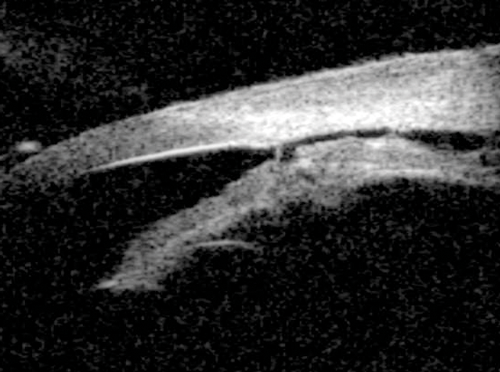

Figure 5: The peripheral iris is concave (bows backwards) in pigment dispersion syndrome.

Pigment dispersion syndrome (PDS)

PDS results from the dissemination of pigment granules from the posterior surface of the iris as a result of friction between it and the zonules and / or lens. PDS typically demonstrates an open angle and iris concavity with reverse pupil block consistent with the hypothesis that irido-zonular chafing is responsible for the dispersion of pigment particles (Figure 5).